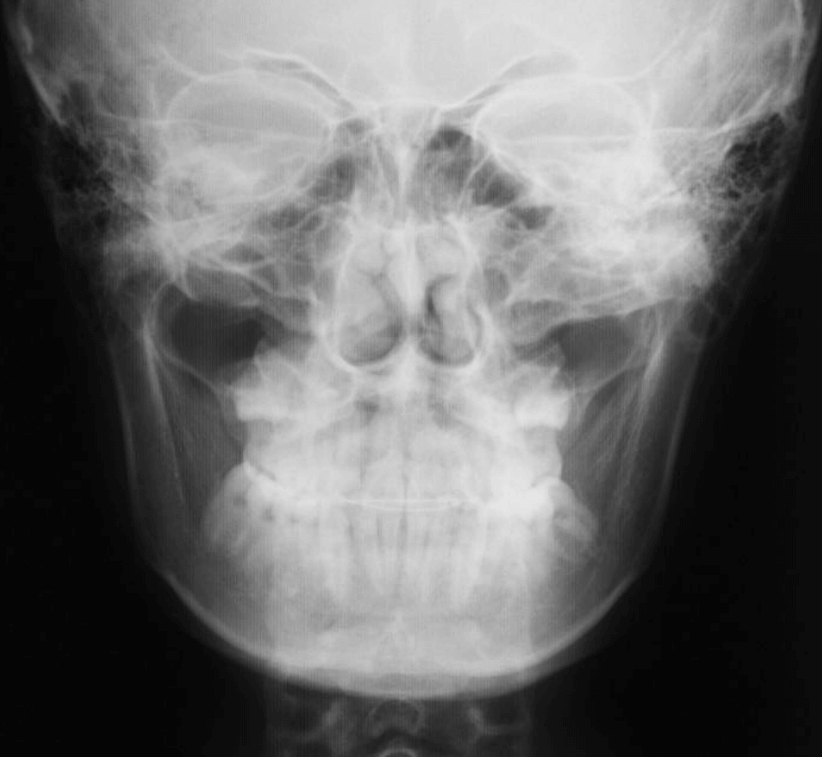

| 年齢・性別 | 11歳1ヶ月の女性 |

|---|---|

| 主訴 | 口元の突出感と歯並びが気になり、将来的な咬合状態を整える目的で来院された患者様です。 |

| 治療期間・回数 | 2年6ヶ月・25回 |

| 費用 | 720,000円 |